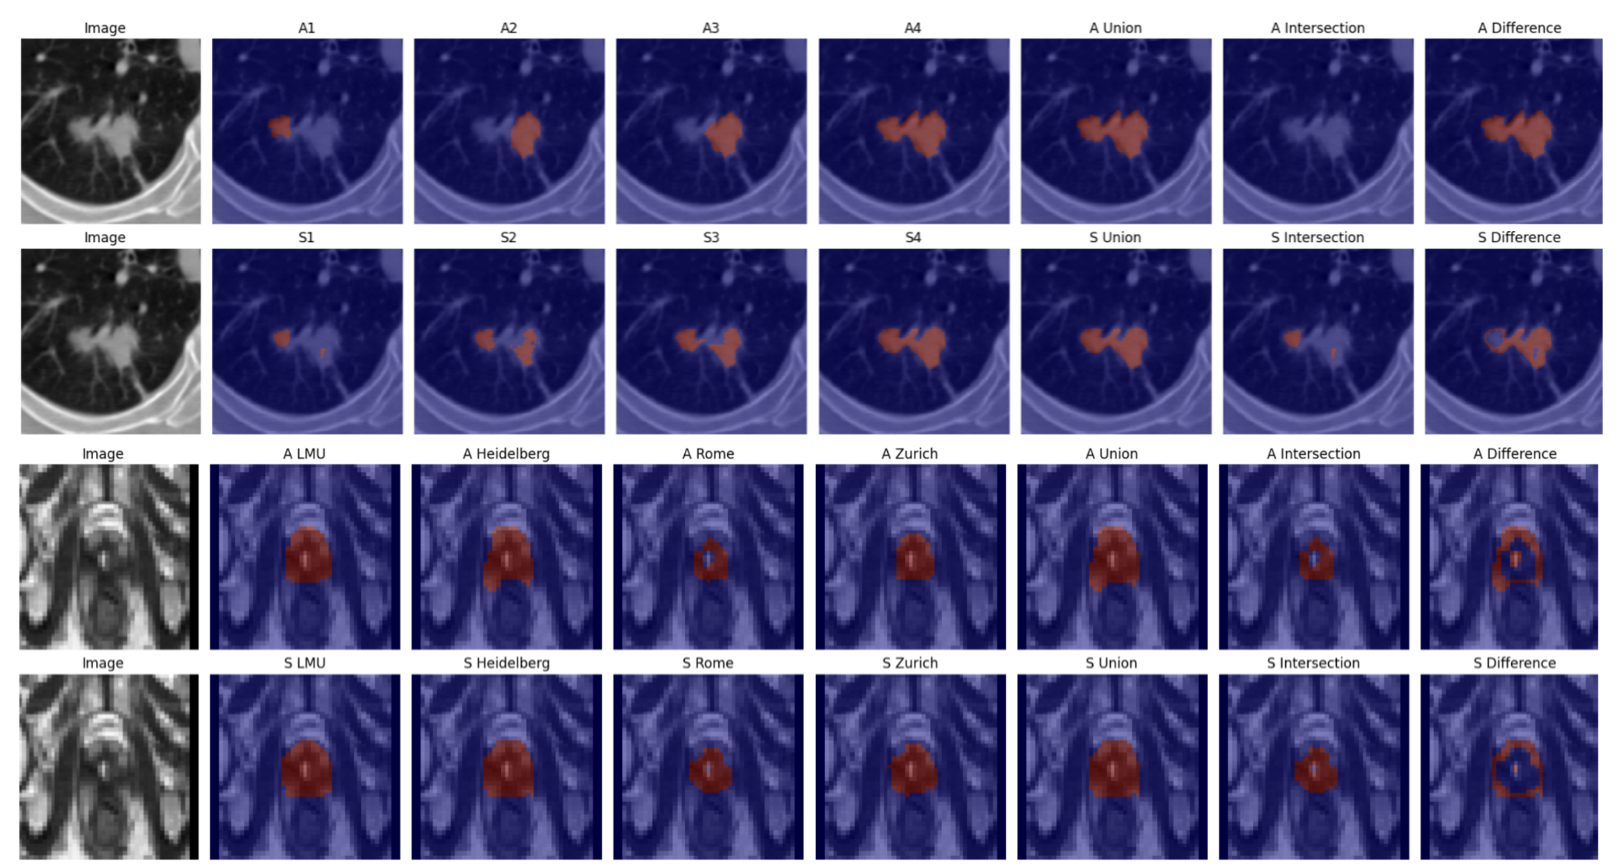

Refer to caption

Fig. 3: Qualitative examples of ProSona on LIDC–IDRI (top) and prostate MRI (bottom). Top: input CT slice with expert annotations (A1,A2,…) and their union/intersection regions. Bottom: predictions (S1,S2,…) guided by prompts describing annotator styles.

Figure 3 shows prompt-conditioned segmentations for both datasets: given prompts such as “conservative radiologist” or “inclusive radiologist,” ProSona reproduces subtle boundary differences matching expert tendencies.